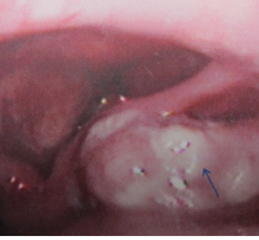

查体:喉外形正常,甲状软骨无增厚、压痛,右侧甲脊音减弱,左侧甲脊音正常,环甲膜无隆起,张口及伸舌无受限。间接喉镜示:左侧声带活动度正常,右侧声带固定于旁正中位,声门闭合欠佳。右侧梨状窝可见较大菜花状新生物,左侧梨状窝光滑,未见明显积液和新生物。右颈Ⅱ区触及肿大淋巴结,约12 mm×22 mm,质稍硬,边界清,活动欠佳,余颈部未触及明显肿大淋巴结。